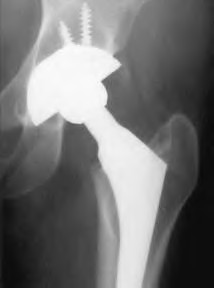

An 82-year-old woman falls and sustains the fracture shown in figure A. She denies any history of dislocation or prodromal pain prior to her fall. What is the most appropriate treatment?

The radiograph demonstrates a periprosthetic femur fracture extending to the tip of the stem. The long spiral fracture is consistent with a loose implant. The bone stock is sufficient. Therefore, this fracture pattern would classify as a B2 using the Vancouver classification system. The Vancouver classification for periprosthetic femoral fractures is simple yet incorporates all the pertinent factors such a location, stem fixation, and bone stock. Type A is a trochanteric fracture- lesser or greater. These can be treated non-operatively usually and ORIF if symptomatic. Type B fractures are around or just below the stem and are subdivided into three types. Type B1 is a fracture with a well fixed stem.

The treatment is cable plating or allograft struts or a combination of the two. Type B2 is a fracture with a loose stem with good bone stock. The treatment is a cementless porous coated long stem atleast two diameter length past the

fracture site. Type B3 is a fracture with a loose stem and comminution. For younger patients, use cementless porous coated long stems with allograft struts. For older patients, consider a tumor prosthesis. Cement fixation is sometimes necessary Type C is a fracture well below the stem tip. These can be treated independently of the prosthesis.

Springer et al showed optimal outcomes with revision involving long extensively-coated femoral stems for Vancouver B fractures.

Masri et al review the classification and treatment of periprosthetic femur fractures.